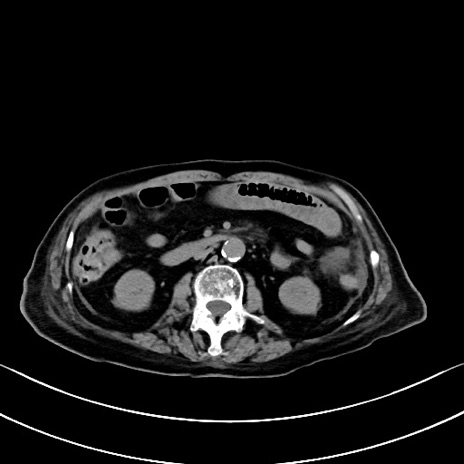

症例40(横断像)他院1日前

横断像